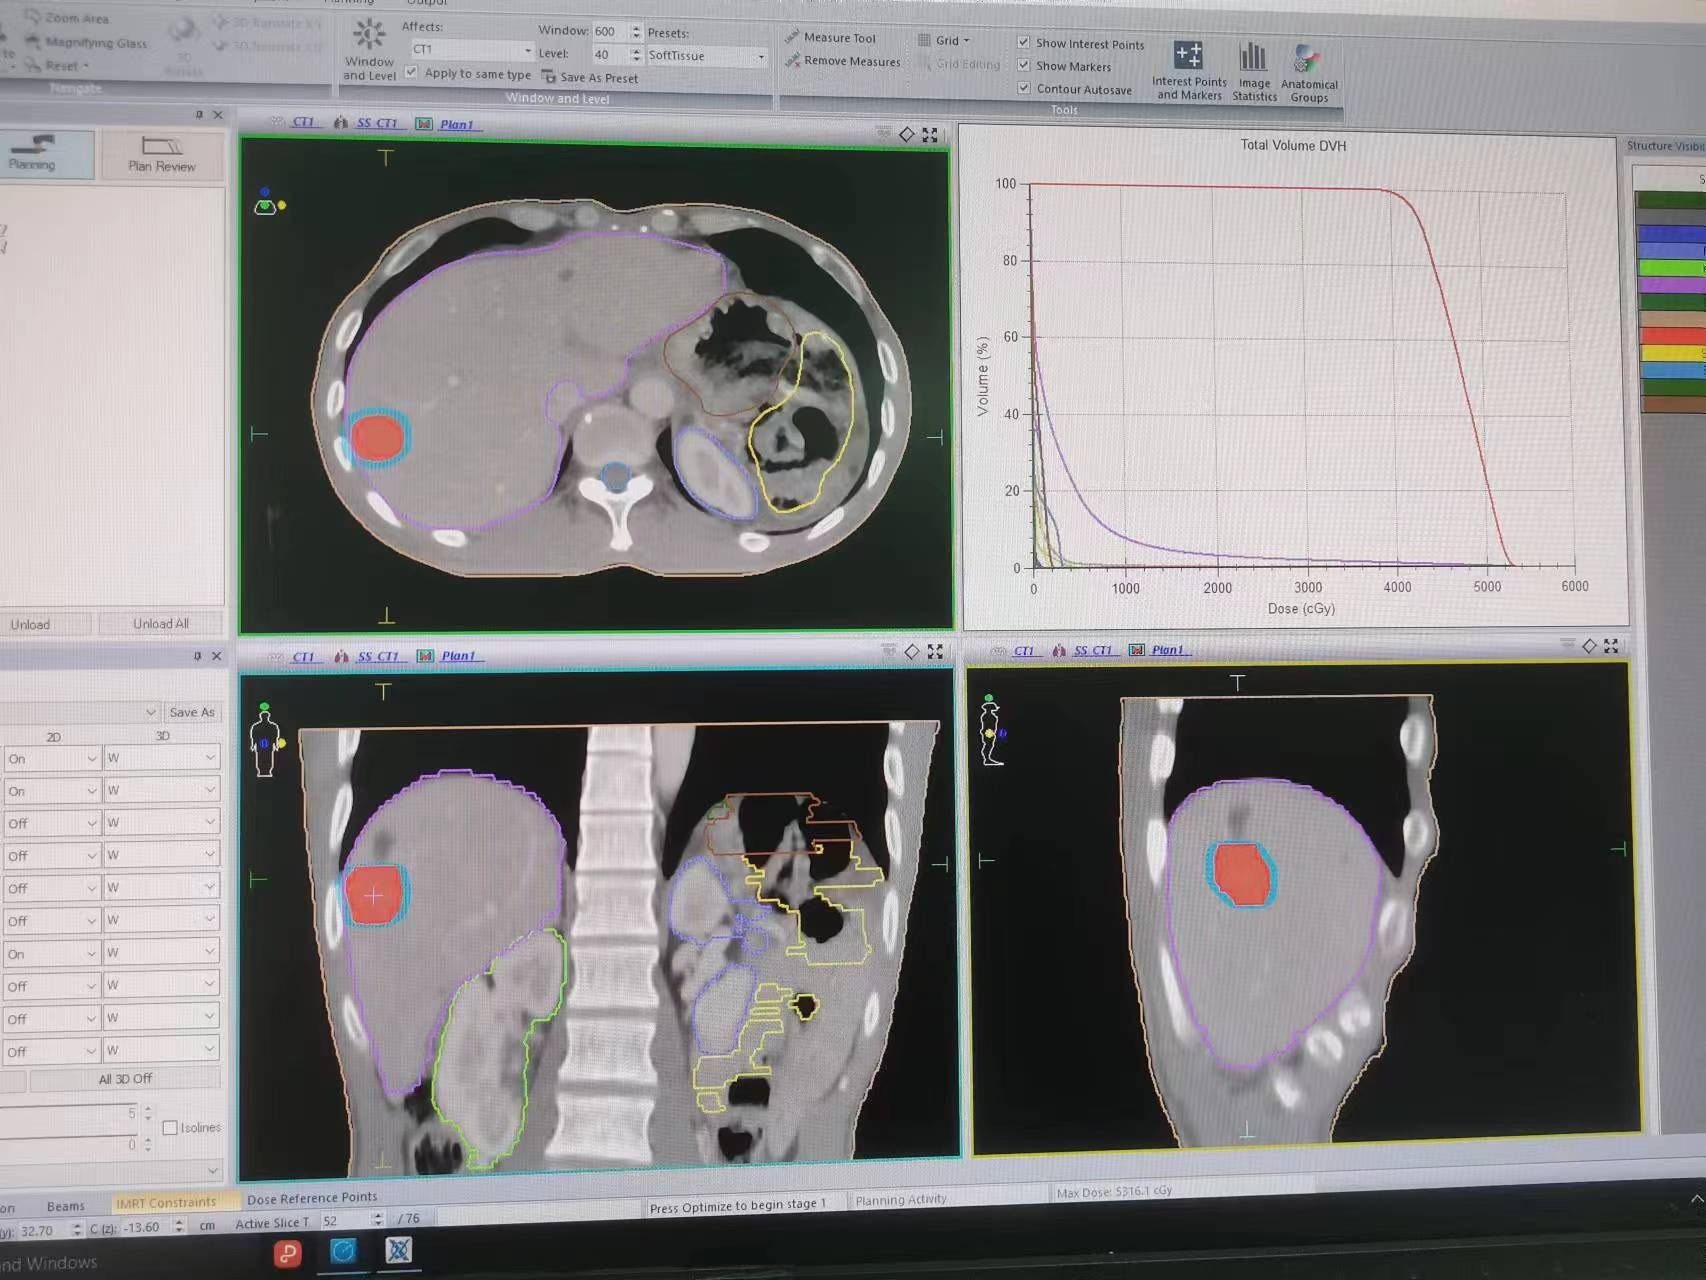

3. 将CT扫描得到的图像导入治疗计划系统,由医生勾画靶区及确定放射治疗方案。物理师制作放射治疗计划后经医师审核批准后传至治疗服务器待用。

2.肝脏肿瘤及肝转移病灶,孤立性或小于3个以内,肿瘤小于5cm的SBRT(X刀)放射治疗SBRT放射治疗。目的是缩短治疗流程、提高肿瘤靶区剂量、增加治疗疗效,降低放射性肝损伤及胃肠副反应。